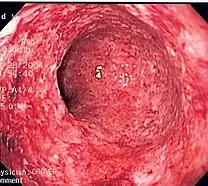

- Fibrinous inflammation: Inflammation resulting in a large increase in vascular permeability allows fibrin to pass through the blood vessels. If an appropriate procoagulative stimulus is present, such as cancer cells,[9] a fibrinous exudate is deposited. This is commonly seen in serous cavities, where the conversion of fibrinous exudate into a scar can occur between serous membranes, limiting their function. The deposit sometimes forms a pseudomembrane sheet. During inflammation of the intestine (pseudomembranous colitis), pseudomembranous tubes can be formed.